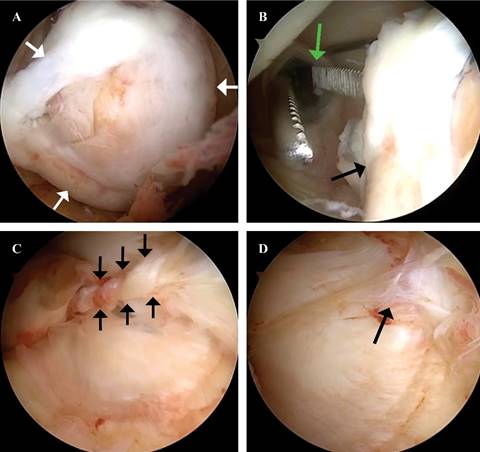

Se realizó una artroscopía de rodilla izquierda (Figura 2), sin encontrar lesiones meniscales, condrales o ligamentarias; sin embargo, al acceder al espacio posterior por portal posteromedial y posterolateral, se visualizó una masa adherida a la cápsula posterior, de forma irregular, con áreas nodulares y una superficie de color café amarillento. Ante estos hallazgos, se decidió establecer un portal posteromedial para realizar el desbridamiento periférico posterior y la exéresis completa de la lesión logrando la resección sin dificultades (Figura 3); se envió a patología transoperatoria confirmando bordes libres, con su posterior análisis por dicho servicio, revelando que los fragmentos de tejido examinados corresponden a una proliferación fibrohistiocítica con patrón de crecimiento nodular, tejido fibroconectivo con numerosos histiocitos cargados de pigmento de aspecto hemosidérico y extensas áreas de hialinización, además de bordes libres. Estos hallazgos son consistentes con el tumor tenosinovial de células gigantes tipo localizado (Figura 4).

Figura 2: Artroscopía de rodilla izquierda, visión anterolateral. A) Tumor localizado en compartimento posterior (flechas blancas). B) Localización del portal posteromedial (flecha blanca) en relación a tumor (flecha negra). C) Pedículo de tumor unido a cápsula posterior (flechas negras). D) Visualización posterior a exéresis (flecha negra).